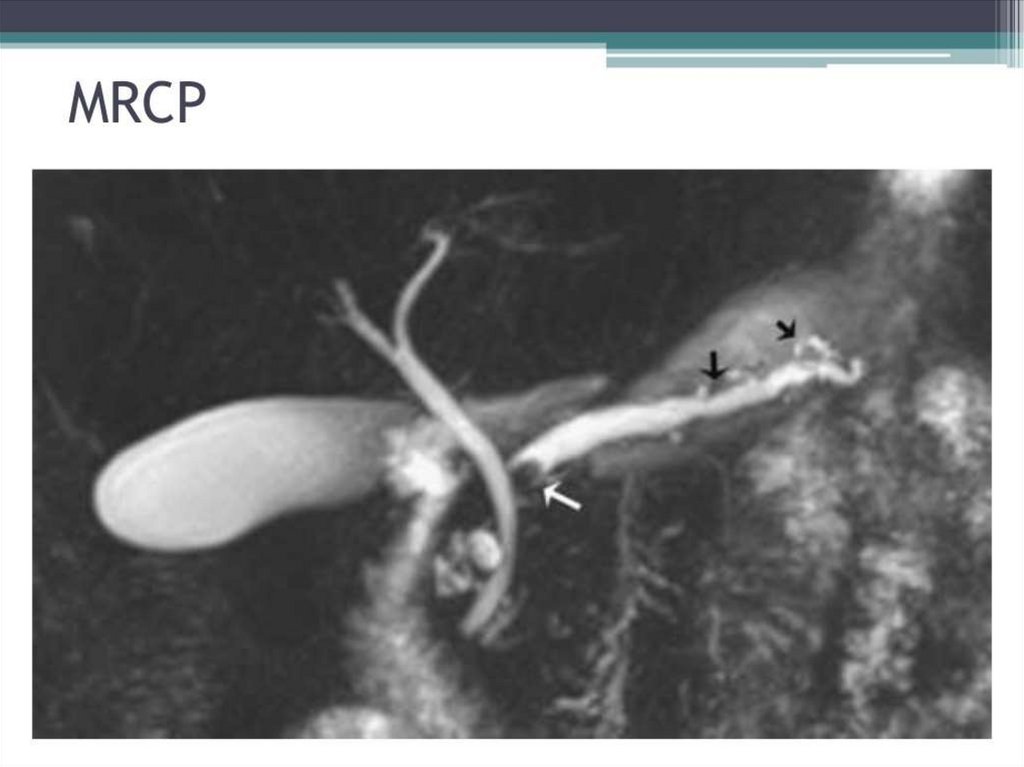

Chronic pancreatitis